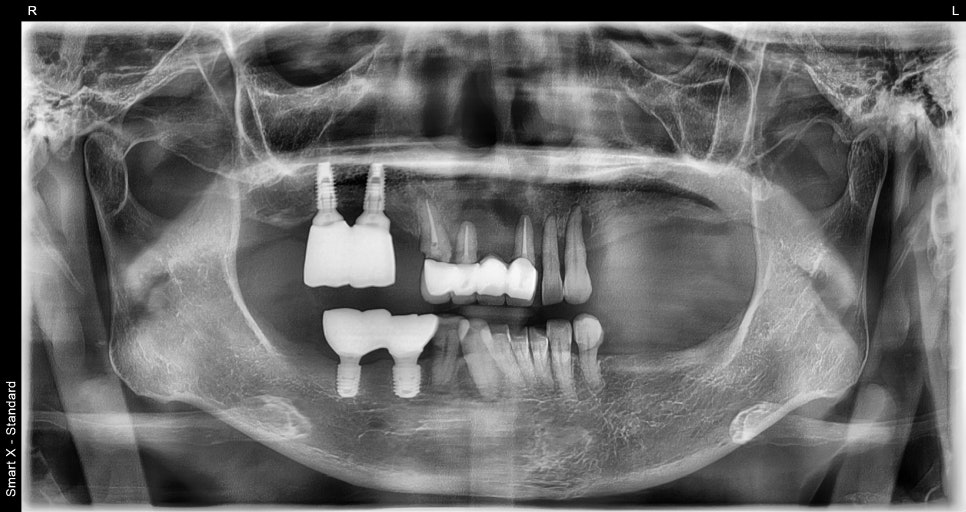

Condition at the first visit

Before full-mouth implants

The patient had weakened teeth in several areas, including the front teeth and molars,

and the remaining teeth were also loose or broken,

so they were barely functioning.

In particular, many molar areas were already missing teeth,

making it difficult to eat anything other than soft foods.

After a detailed examination,

we found that the overall periodontal structure had collapsed significantly,

making recovery with partial treatment difficult.

Detailed analysis based on CT diagnosis

At Seoulove Dental Hospital,

we use 3D CT and an oral scanner

to analyze the bone thickness, degree of resorption, nerve position, gum height,

and occlusion.

The test results showed that in several areas of both the upper and lower jaws,

the bone had been significantly resorbed,

and

bone grafting (GBR) was absolutely necessary in multiple areas in order to place implants.